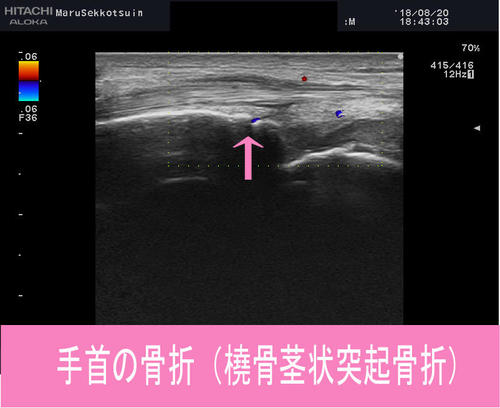

手首の骨折(橈骨茎状突起骨折)

診断結果は、橈骨茎状突起の不全骨折でした。

エコーで骨折部を確認し、的確に骨折部位を把握し、

"橈骨茎状突起骨折"あまり聞きなれないと思いますが、

橈骨という前腕の骨の先っちょの骨折で、

「転倒して手を突いた」という場合にたまに起こります。